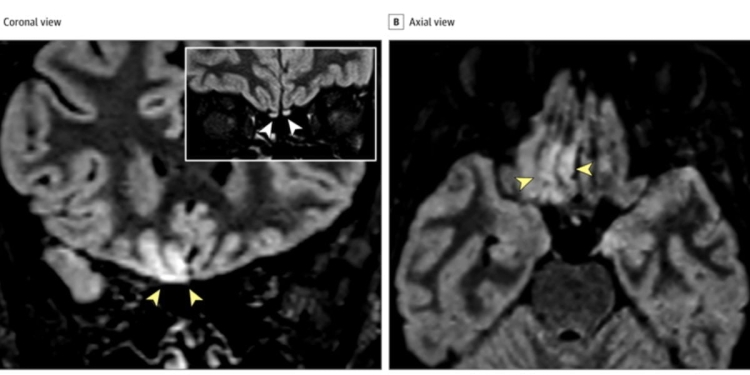

Come cambia il cervello dopo il coronavirus? Il professor Letterio Salvatore Politi, dell’IRCCS Istituto Clinico Humanitas di Milano, ha provato a dare una risposta con uno studio firmato insieme a Ettore Salsano e Marco Grimaldi, e pubblicato su Jama Neurology. Hanno esaminato la risonanza magnetica di una 25enne affetta dal Covid-19 che ha perso l’olfatto, uno dei sintomi riconosciuti del coronavirus. Si stima infatti che il 65 per cento delle persone infette lo riportino. Dall’esame non sono emersi segni particolari al torace, ma le zone del cervello che regolano l’olfatto hanno mostrato delle anomalie. Ed è la prima volta che una risonanza magnetica cattura i cambiamenti nel cervello causati dal coronavirus (anche se non accade per tutti i pazienti), rivelando come il virus Sars-CoV-2 possa modificare questo organo e privare le persone dell’olfatto. Questo studio è la prova di come non attacchi solo le nostre vie aeree, ma anche il cervello. Le immagini mostrano, infatti, leggere fluttuazioni nell’area del cervello che controlla questo senso.

Un occhio non esperto fatica a scorgere questi cambiamenti, ma gli esperti li hanno subito individuati nella risonanza magnetica di una radiologa 25enne. La giovane era in buona salute fino a quando nel suo ospedale non sono arrivati pazienti affetti da coronavirus. Per un giorno l’operatrice sanitaria ha avuto tosse secca, poi è sparita. Poi però non è riuscita a percepire alcun odore, inoltre tutto quello che mangiava o beveva aveva un sapore strano. Tutto ciò pur non avendo sviluppato febbre. Gli esami al torace non hanno evidenziato problemi tre giorni dopo l’alterazione dell’olfatto, quindi i medici hanno eseguito la risonanza magnetica al cervello, trovando alterazioni in due aeree: lobo frontale e bulbi olfattivi. Dopo 28 giorni, è stata eseguita un’altra risonanza che ha invece mostrato come il cervello tornava alle condizioni precedenti, anche se i bulbi olfattivi apparivano leggermente infiammati. «In base ai risultati, possiamo ipotizzare che il coronavirus possa invadere il cervello attraverso la via olfattiva e causare una disfunzione», hanno scritto gli autori dello studio.